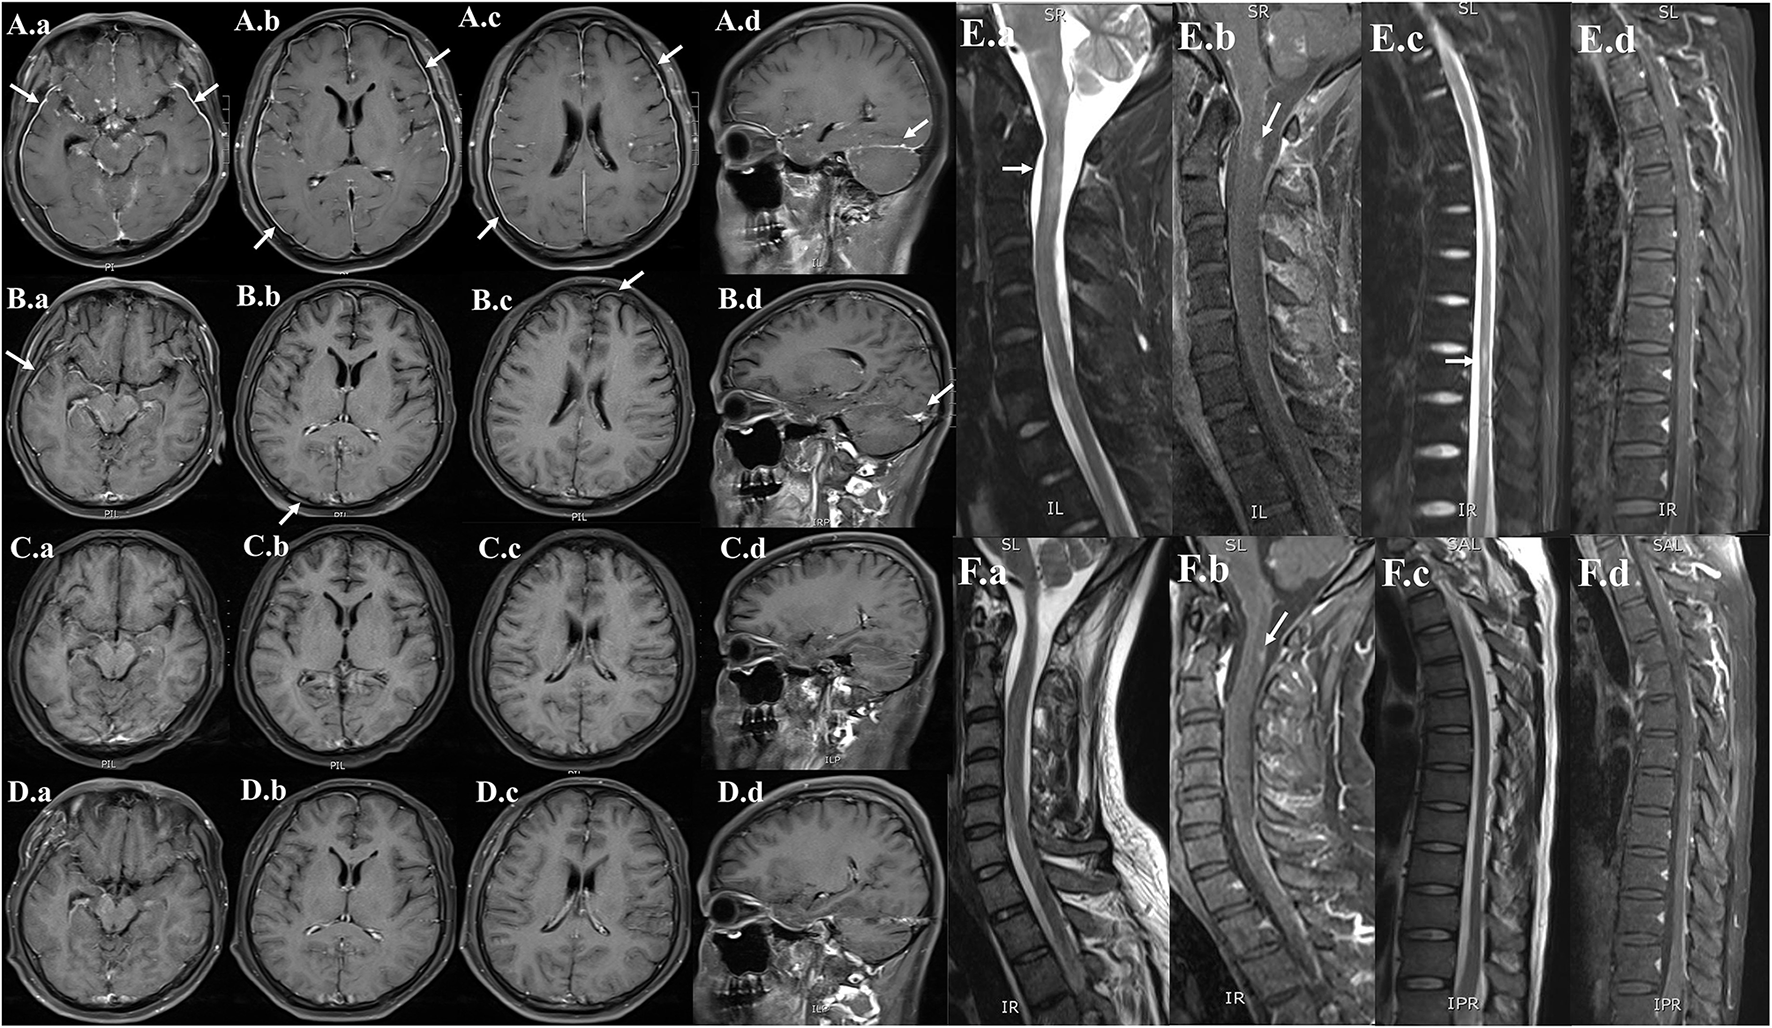

Figure 3

Serial neuroimaging with MRI demonstrating lesion amelioration. (A) Contrast-enhanced MRI brain (hospital day 5), (a,b,c) axial and (d) sagittal T1-weighted images showing diffuse leptomeningeal and pachymeningeal contrast enhancement (white arrows). (B) Repeat MRI on hospital day 29, (a,b,c) axial and (d) sagittal views showing less meningeal enhancement after 3 weeks of therapy. (C) Repeat MRI on the time of discharge (hospital day 62), (a,b,c) axial and (d) sagittal views showing the obvious resolution of the previous meningeal enhancement. (D) Repeat MRI on 6-month follow-up (a,b,c) axial and (d) sagittal views showing no meningeal enhancements. (E) MRI of the cervical and thoracic spine (hospital day 5), (a,c) sagittal T2-weighted and (b,d) post-contrast T1-weighted showing abnormal longitudinally extensive T2 weighted hyperintensities involving the C2–C3 and T6–T9. Partial enhancement was observed in the dorsal aspect of the spinal cord at C2 and T6–T7 levels (white arrows). (F) Repeat MRI on hospital day 29, (a,c) sagittal T2-weighted and (b,d) post-contrast T1-weighted images showing lesser abnormal hyperintensities compared with previously.

On day 5 after admission, the cytology testing of CSF revealed 4% lymphocytes, 2% monocytes, and 94% atypical cells (Figure 2A). Brain MRI with contrast was reported as multiple abnormal signals in the cortex, extensive pachymeningeal enhancement, and irregular thickening (Figure 3A). The Magnetic resonance venography and diffusion-weighted imaging were normal. MRI of the cervical and thoracic spine showed T2 hyperintense lesions located at C2–C3 and T6–T9, with partial enhancement (Figure 3E).

Based on the positive mNGS and confirmatory qRT-PCR test, a final diagnosis of VZV meningoencephalitis with meningomyelitis was made. The patient received an additional foscarnet sodium (3g q12 h) on day 7 after admission. The combined use of acyclovir and foscarnet sodium resulted in a steady improvement in symptoms. After combination therapy, repeated CSF studies on day 19 after admission revealed 95% lymphocytes and 5% monocytes. Meanwhile, no atypical cells were found in the cytology testing of CSF (Figure 2B). On day 7 after admission, the skin varicella showed gradual recovery. A repeated MRI on day 29 after admission showed less meningeal enhancement (Figures 3B,F). During the entire treatment course of hospitalization, we did not use steroids.

By the time of discharge (hospital day 62), the patient was conscious, and denied headache fever. No fever and seizure occur during hospitalization. Examination revealed normal eye movements, normal strength/sensation, normal coordination/gait testing, and no nuchal rigidity. But the Kernig's sign and left-sided Babinski's sign were still positive. Repeated CSF studies revealed a clear appearance, pleocytosis (18 total nucleated cells/μl), and elevated protein (1.2 g/L). Compared with the CSF on admission, the pleocytosis and elevated protein were significantly alleviated. A repeated brain MRI revealed obvious resolution of the previous abnormal pachymeningeal enhancement (Figure 3C). At the 6-month follow-up visit, he denied headache, nausea, vomiting, diplopia, and confusion. Repeated CSF studies revealed normal cell count and protein (Table 1). The repeated brain MRI revealed no abnormal meningeal enhancement (Figure 3D).

Furthermore, the CSF protein level in our case is also significantly increased (10.326 g/L), which gradually decreased after acyclovir therapy. Generally, high protein concentration in the CSF is non-specific. However, a protein level of more than 10 g/L in viral meningoencephalitis is rare, which is mainly reported in HIV-positive patients (15, 16) and patients with leukemia (7) or malignant lymphoma (17). Particularly, in a patient with a history of AML, the markedly elevated protein in CSF may suggest CNS leukemia rather than viral etiology. Our case emphasizes the utility of taking mNGS and qRT-PCR to detect potential viral causes, even the extremely elevated protein level in CSF. Moreover, brain MRI in our patient showed diffuse pachymeningeal enhancement, which is an unusual meningeal enhancement in viral meningoencephalitis. Repeat brain MRI after acyclovir therapy revealed obvious resolution of the abnormal pachymeningeal enhancement. In total, there are three points in our case that differ from most viral meningoencephalitis with meningomyelitis: (1) the presence of CSF atypical cells. (2) The extremely high protein concentration in the CSF (more than 10 g/L). (3) The diffuse pachymeningeal enhancement in brain MRI.